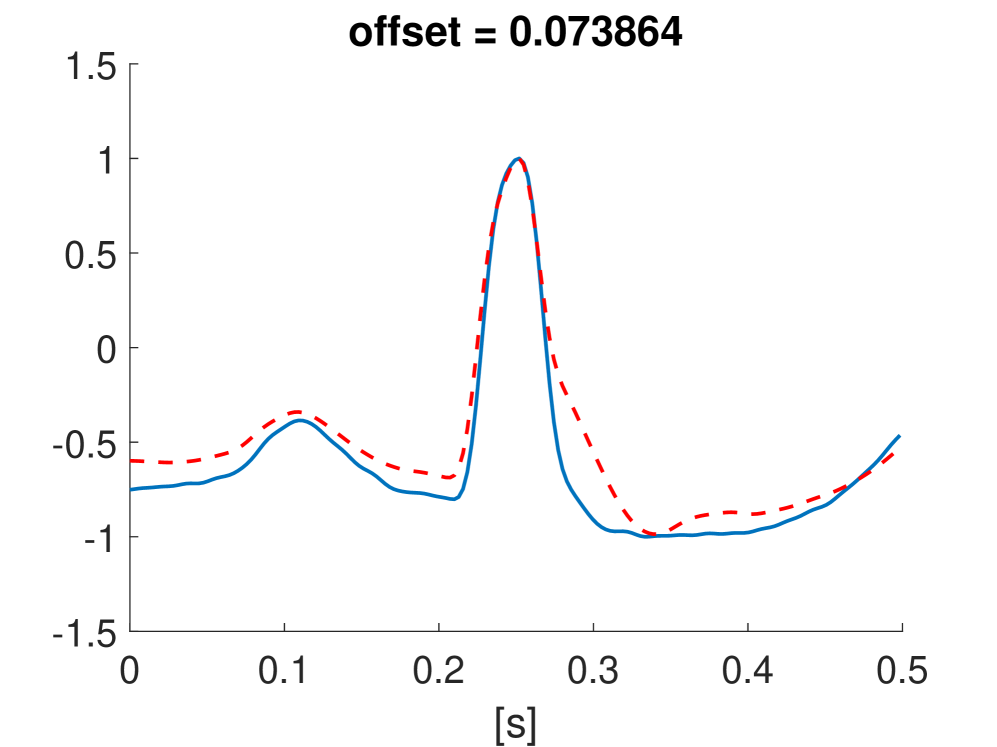

Fig. 10 shows the result in input space of moving along the first principal components in the latent feature space. As original base point we take a normal beat signal, i.e. corresponding to a hidden unit on the bottom right of Fig. 9(a). The smooth transition between the beat patterns allows for interpretation of the first principal components. This allows a clinical expert to understand on what basis the paced beats are separated by the principal components and if this basis has a physiological meaning. In order to investigate the separated region of the latent space at the top of Fig. 9(b) we start from a paced beat pattern and vary along the third principal component. This allows us to see which sort of heartbeat patterns are responsible for this specific distribution in the latent space.